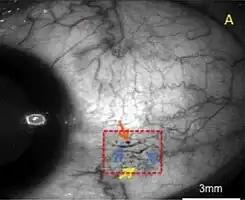

A case of conjunctival microangiopathy (red dashed-square) secondary to diabetes demonstrating a microaneurysm (orange arrow), vessel dilatation (blue arrows), and vascular tortuosity (yellow arrow). | |